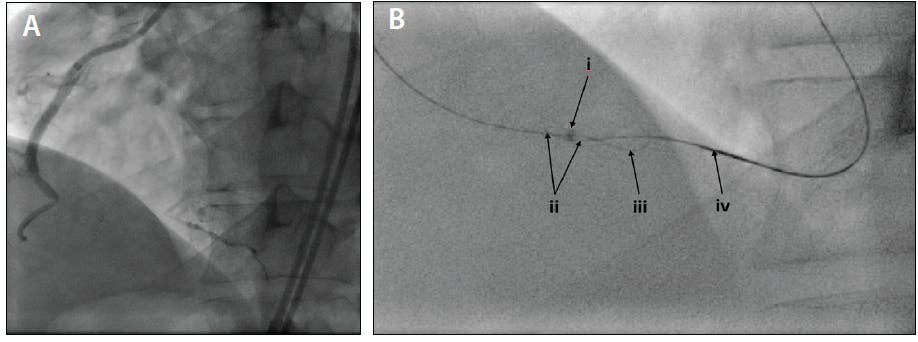

Reverse CART CTO application. Using a GC extension in the antegrade (occluded) vessel has a number of benefits. The extension is passed into the subintimal space in an antegrade fashion using the inchworm technique. It is essential to avoid antegrade injection at this time. The retrograde wire is then advanced into the extension, rather than requiring reentry into the GC (Figure 3; see Video). This allows antegrade balloon inflation to be performed just ahead of the extension, thus minimizing the length of subintimal space to traverse with the retrograde wire. It also allows for a standard-length retrograde GC by shortening the total distance for the retrograde microcatheter.4 Additionally, this avoids the risk of extending the dissection into the aorta or dissecting past and occluding a major side branch, especially if the CTO is in the left coronary artery (LCA).

Figure 3. CTO in the distal RCA (A). A GC extension in reverse CART CTO (B): GC extension in the subintimal space within the occluded segment (i), the retrograde guidewire in the subintimal space advanced into the GC extension (ii), the antegrade guidewire in the subintimal space (iii), and the retrograde microcatheter (iv).